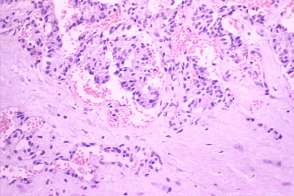

Histopathology: medullary cancer.